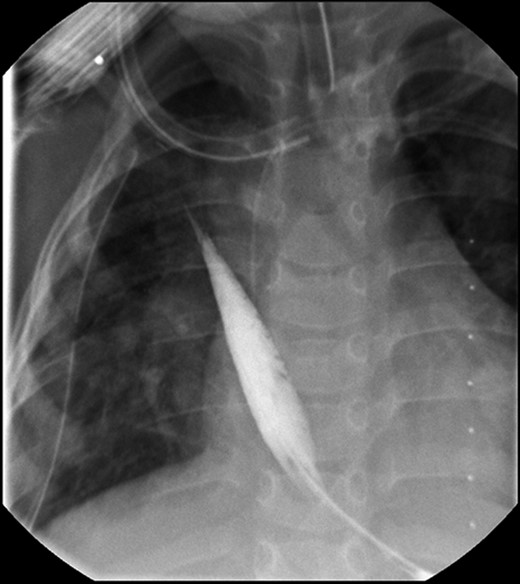

With the distal colon graft in place, as well as the distal esophageal segment, we recommended a combined procedure with graft removal and growth induction given the 8.2-cm gap (Fig. 1A and B). A thoracoabdominal incision was made and the colonic conduit was dissected away from the diaphragm; extensively mobilized from the left lateral segment of the liver and lung; and, transected from its anastomosis with the stomach. The stomach was then repaired in two layers. Traction sutures, using 4.0 prolene sutures, were then placed in the muscular layer of the distal esophageal segment and brought out onto the chest wall.

(A) Lateral view during her initial fluoroscopic examination illustrating a small, distal (lower) esophageal remnant present in situ (Black arrows). Contrast was injected through her existing gastrostomy tube. (B) Anterior–posterior (AP) view during initial fluoroscopic examination illustrating an aperistaltic, native colonic interposition in situ with significant dilatation.